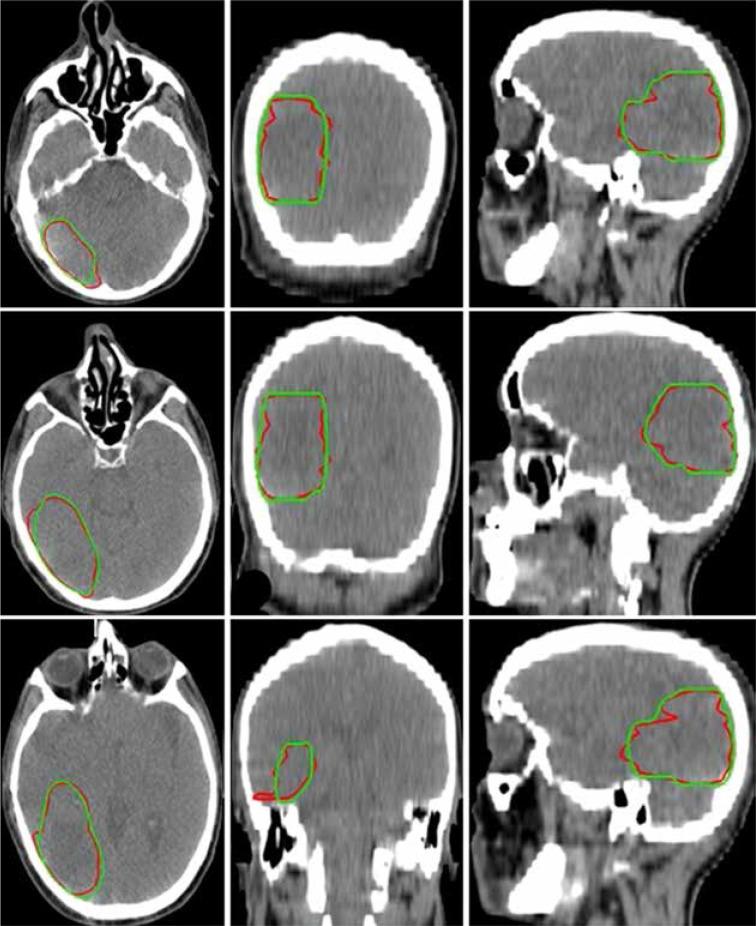

In this study, the modified Segmentation-Net (SegNet) model with deep supervision and residual-based skip connection mechanism was trained on 259 glioblastoma patients from the Multimodal Brain Tumour Image Segmentation Benchmark (BraTS) 2019 Challenge dataset for segmentation of gross tumour volume (GTV). Then, the pre-trained CNN model was fine-tuned with an independent clinical dataset ( = 37) to perform the CTV segmentation. In the process of fine-tuning, to generate a CT segmentation mask, both CT and MRI scans were simultaneously used as input data. The performance of the CNN model in terms of segmentation accuracy was evaluated on an independent clinical test dataset ( = 15) using the Dice Similarity Coefficient (DSC) and Hausdorff distance. The impact of auto-segmented CTV definition on dosimetry was also analysed.

The proposed model achieved the segmentation results with a DSC of 89.60 ± 3.56% and Hausdorff distance of 1.49 ± 0.65 mm. A statistically significant difference was found for the Dmin and Dmax of the CTV between manually and automatically planned doses.

在本研究中,具有深度监督和基于残差的跳跃连接机制的改进型分割网络(SegNet)模型在来自多模态脑肿瘤图像分割基准(BraTS)2019挑战赛数据集的259例胶质母细胞瘤患者上进行训练,以分割肿瘤总体积(GTV)。然后,使用一个独立的临床数据集(n = 37)对预训练的CNN模型进行微调,以执行CTV分割。在微调过程中,为了生成CT分割掩码,CT和MRI扫描同时用作输入数据。使用骰子相似系数(DSC)和豪斯多夫距离,在一个独立的临床测试数据集(n = 15)上评估CNN模型在分割准确性方面的性能。还分析了自动分割的CTV定义对剂量测定的影响。

所提出的模型实现了分割结果,DSC为89.60 ± 3.56%,豪斯多夫距离为1.49 ± 0.65 mm。在手动计划剂量和自动计划剂量之间,CTV的Dmin和Dmax存在统计学显著差异。